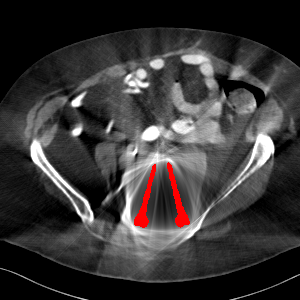

Visual comparison. As shown in Fig. 5, metallic implants such as spinal rods and hip prosthesis cause severe streaky artifacts and metal shadows, which obscure bone structures around them. cGan-CT cannot recover image intensity correctly for both cases. Sinogram domain or dual-domain methods perform much better than cGan-CT. LI, NMAR, and CNNMAR introduce strong secondary artifacts and distort the whole images. In NMAR images, there are fake bone structures around the metals, which is related to segmentation error in the prior image from strong metal artifacts. The segmentation error is also visible in NMAR sinogram. CNNMAR cannot restore the correct bone structures between rods in case 1. The tissues around the metals are over-smoothed in DuDoNet because LI sinogram and image are used as inputs, and the missing information cannot be inferred later. Our model retains more structural information than DuDoNet and generates anatomically more faithful artifact-reduced images.

Visual comparison. Fig. 7 shows two clinical CT images with metal artifacts. Case 1 is with moderate metal artifacts. cGan-CT does not suppress the artifacts completely and generates some fake details. LI, NMAR, CNN-MAR remove all the artifacts but introduce new streak artifacts, which is caused by the discontinuity in the corrected sinogram. DuDoNet outputs over-smoothed sinogram, which leads to blurred tissues close to the metal implants, such as muscle and bone. Only our model can provide realistic enhanced sinogram and remove the artifacts while retaining the structure of nearby tissues. Case 2 is very challenging as the rods bring strong metal shadows and bright artifacts around the vertebra. cGan-CT recovers the shape of vertebra but changes the overall image intensity. Other sinogram inpainting methods fail as the soft tissue and bone near the rods are heavily distorted. Our model removes part of the dark bands and reproduces correct anatomical structures around the rods.